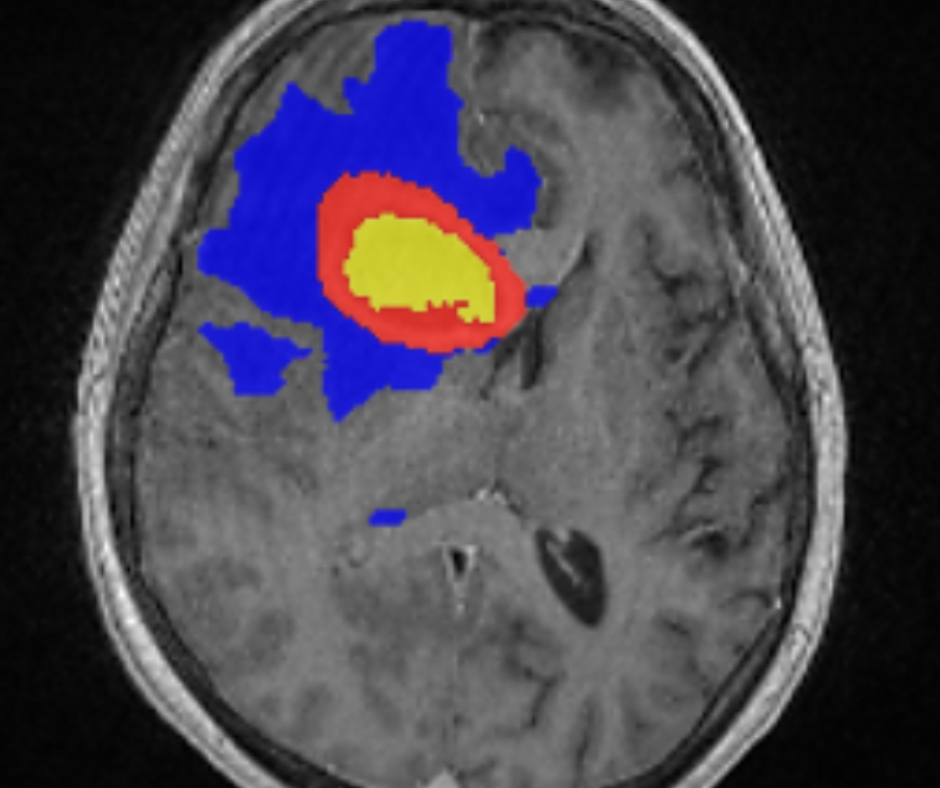

The Maestro Brain Model reportedly provides automated identification, quantification and labeling of brain structures on magnetic resonance imaging (MRI).